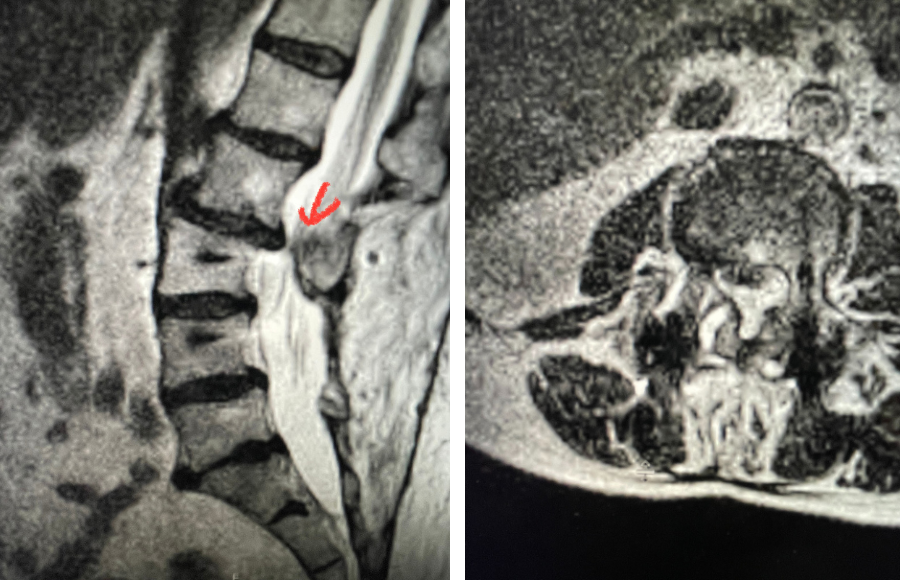

This 42-year-old female presented after complaining of low back pain with intermittent pain going down her left leg and numbness of her feet. She reported having a fall on her back about ten years ago and since then has had back pain. On exam, she had ⅘ weakness of her left dorsiflexion and extensor hallucis longus weakness. MRI revealed a “garden variety” L4-5 grade 1 spondylolisthesis with stenosis, although it was read as having a left pedicle “stress reaction” and suspicion of bilateral spondylotic defects. This was an interesting reading of the MRI, as it is uncommon to have spondylotic defects at L4 which occurs 5-15% versus at L5 which occurs in 85-95% of cases. Most people have an L5-S1 spondylolisthesis with an L5 pars defect. There was thickened ligamentum flavum worse on the left adjacent to the facet with concentric stenosis and bilateral foraminal stenosis. She had tried physical therapy and epidural injections, which did not help. She had trouble standing for long periods of time. Neurologically, she was intact.

Plain lumbar x-rays were done with flexion/extension views. Surprisingly the patient had 4 mm of anterior translation and slight angulation in flexion (Fig 1). This was unexpected because in degenerative spondylolisthesis the patient more commonly has auto stabilized by formation of stabilizing arthritic structures and has no motion on dynamic x-rays. However, approximately 20% of patients will have some degree of translation on flexion-extension x-rays with degenerative L4-5 spondylolisthesis. Because she had failed all means of conservative management, it was felt that the patient would benefit by a lumbar decompression and instrumented fusion because of the acute instability demonstrated on x-rays and her age.

Fig 4: Sagittal and axial T2-weighted lumbar MRI images demonstrating severe next segment degeneration and stenosis at L2-3 above prior L3-5 fusion. Note retrolisthesis and significant facet arthropathy at L2-3 (red arrow).